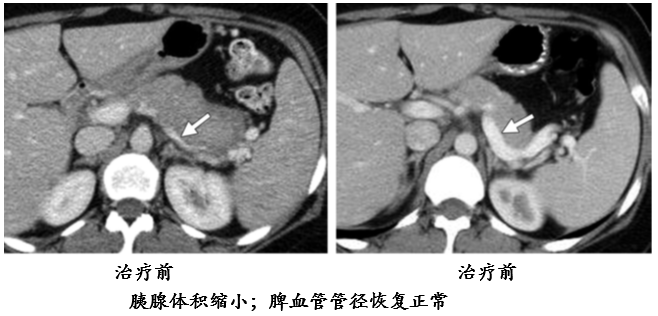

在影像学鉴别困难时,可结合类固醇激素实验性治疗,必要时结合血清学 IgG4 水平做出分析。

糖皮质激素治疗有效,能够使受累器官和组织恢复到原来的状态